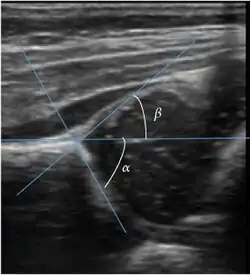

Ultrasound

Ultrasound is the first-choice technique for diagnosis of newborns hip dysplasia. In experienced hands with appropriate technology, ultrasound can also be useful during the first year of life. Some European healthcare systems encourage universal ultrasound screening in neonates between the sixth and eighth weeks. Although it shows higher initial costs caused, it leads to significant reduction in the total number and overall costs of dysplastic hips undergoing operative and nonoperative treatment.[1]

Ultrasound allows categorizing pediatric hips, according to Graf’s criteria, in four main types: normal, immature, and dysplastic (subluxed and dislocated). This classification is based on measurements of the acetabular inclination angle (alpha), cartilage roof angle (beta), and infant age. The femoral head coverage can also be determined by dividing the length of the femoral head covered by the acetabular fossa and the diameter of the femoral head. Its lower normal limits are 47% for boys and 44% for girls (Figure 11).[1]

Figure 11:

-

Useful ultrasound measures in neonatal hip sonography, alpha and beta angles.[1] -

Measurement of femoral head coverage.[1]